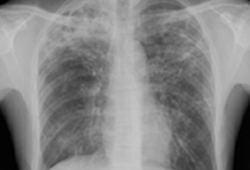

Radiografia torácica

[Figure caption and citation for the preceding image starts]: Radiografia torácica mostrando múltiplas metástases pulmonares miliares (setas). O tumor primário era carcinoma de tireoideE. Dick, Student BMJ. 2001;9:10-12 [Citation ends].